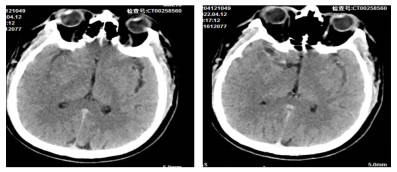

1 资料与方法患者男性,51岁,于2022年4月12日19:50,因突发晕厥,伴左侧肢体无力、言语不清半小时就诊。查体:体温36.3 ℃,呼吸频率20次/min,脉率73次/min,血压118/99 mmHg(1 mmHg=0.133 kPa),SaO2 85%。神志清,精神差,双侧瞳孔等大等圆约3.5 mm,光反射灵敏,口角歪斜,言语不清,左上肢肌力3级,左下肢肌力2级。既往无高血压病史。急诊床旁检验检查示:D-二聚体5.158 µg/mL、肌红蛋白107.86 ng/mL;动脉血气示:PaO2 33.9 mmHg、FO2Hb 64.6%、FHHb 30.1%、k+ 3.3 mmol/L、血乳酸(lactic acid, Lac)3.3 mmol/L,心电图排除ST抬高型心梗,头颅CT示(见图 1):右侧大脑中动脉密度增高,建议MRI及CTA进一步检查。请卒中医生会诊考虑:急性脑梗死和肺栓塞。随后患者出现恶心、呕吐、吐物为胃内容物,20:00血压突降至57/43 mmHg,烦躁不安、口唇、面色苍白、肢体末梢冰冷,给予复方氯化钠注射液500 mL、生理盐水500 mL扩容、生理盐水200 mL+多巴胺注射液200 mg升压治疗,20:14血压95/60 mmHg、SaO2 95%(鼻导管4 L/min)。20:34血压86/53 mmHg,烦躁,呼吸困难,左侧肢体肌力为0级,给予气管插管氧疗。20:50血压100/62 mmHg、SaO2 95%,左侧上、下肢肌力0级,右侧肌力5级,左侧浅感觉较右侧差,深感觉正常,双侧跟、膝腱反射存在,左侧巴彬斯基征(+),余(-)。初步考虑:急性脑梗死和急性肺栓塞。

| 图 1 患者CT头颅平扫 |